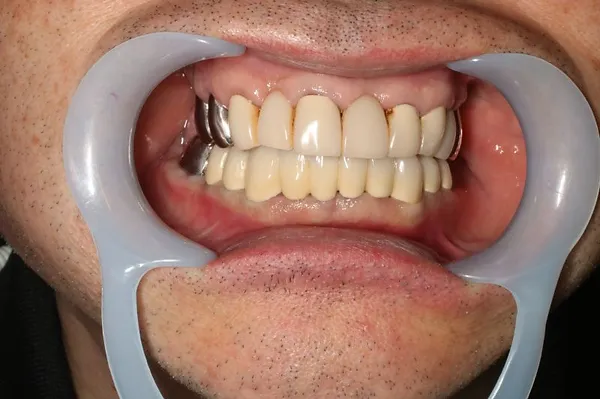

6入れ歯にしないブリッジ治療【ケース1】

H20.6.2のレントゲン

歯槽膿漏の為、上の6本の歯を抜き、上の右端から左端まで繋げたブリッジを作りました。

H31.1.25のレントゲン

H21.2.21に上の歯(ブリッジ)が完成しました。

左の写真は10年ちょっと経過したH31.1.25日に撮影した写真で、経過良好と思われます。

下顎も虫歯と歯槽膿漏のため長く持たせるために左下奥歯の一本を抜歯し残りを繋げて作りました。